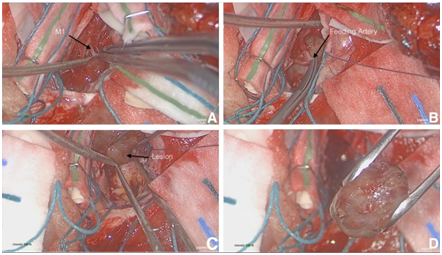

Operative technique

The patient was brought to the operating room for the purposes of diagnosis and cytoreduction. A trajectory centric approach using real time 3D DTI rendering was created (BrightMatter Plan ©, Synaptive Medical Corporation, Toronto, Canada). A transsylvian corridor was ultimately chosen in order to optimize safe resection of the lesion. A robotic optical microscope (Synaptive Medical Corporation, Toronto, Canada) was used for visualization. Using standard microdissection technique and image guidance, the Sylvian fissure was opened proximal to distal. The M1 segment was then isolated. After the circumferential dissection of the mass, an arterial afferent was noted. The pedicle artery was isolated and it ended in the mass itself without an identifiable efferent branch. This pedicle was coagulated and divided. The lesion was then delivered en bloc (Figure 4).

Figure 4 Surgical resection using standard microdissection techniques and image guidance. (A) The M1 segment was isolated. (B) After the circumferential dissection of the mass, an arterial afferent was discovered. The feeding pedicle artery was then isolated, terminating in the mass itself. (C) After the artery was divided, the mass was removed en bloc (D).